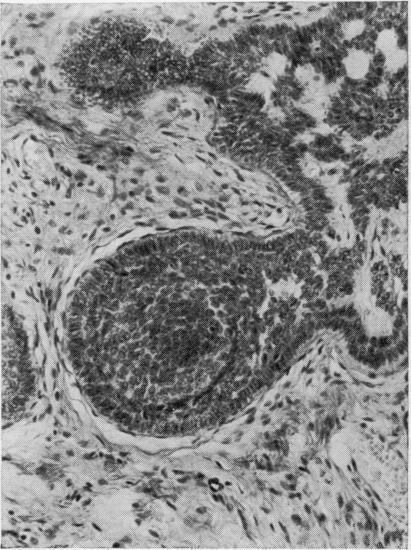

Differentiating neoplasms of hair germ are benign epithelial-mesenchymal tumours of skin in which hair follicle development may be partly or completely recapitulated. The epithelial component is equivalent to the hair germ. The mesenchymal component is equivalent to the dermal papilla. Epithelial-mesenchymal interaction results in the morphogenesis of hair follicles. In neoplasms showing stromal induction, there is centrifugal organizations: hair bulbs are found at the periphery of tumour lobules and hairs are projected centrally to lie within small keratinizing cysts. Neoplasms of hair germ without advanced morpho-differentiation are termed ;trichoblastomas', and those neoplasms in which hair follicle development is advanced are called ;trichogenic trichoblastomas'.

毛母质瘤是皮肤的良性上皮-间叶肿瘤,其中毛囊发育可能部分或完全重现。上皮成分相当于毛母质,间叶成分相当于毛乳头。上皮-间叶相互作用导致毛囊形态发生。在显示间质诱导的肿瘤中,存在离心性结构:毛球位于肿瘤小叶的周边,毛发向中心突出并位于小的角化囊肿内。未发生高级形态分化的毛母质瘤称为“成毛细胞瘤”,而毛囊发育进展的肿瘤称为“毛发生成性成毛细胞瘤”。